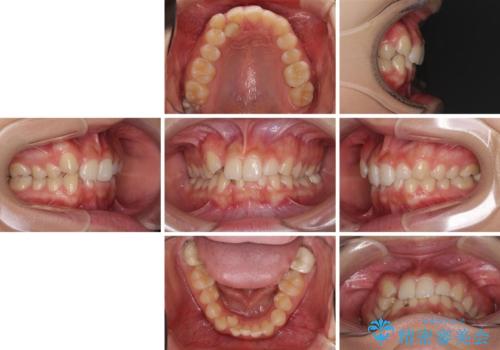

- 上顎の重なっている前歯を気にして来院された患者様です。

八重歯改善には抜歯が必要で、八重歯の移動量が多く、更には右側にずれている正中を改善する必要がありました。

インビザライン単体での治療は困難と判断し、補助装置により八重歯移動後にインビザラインを用いることとしました。